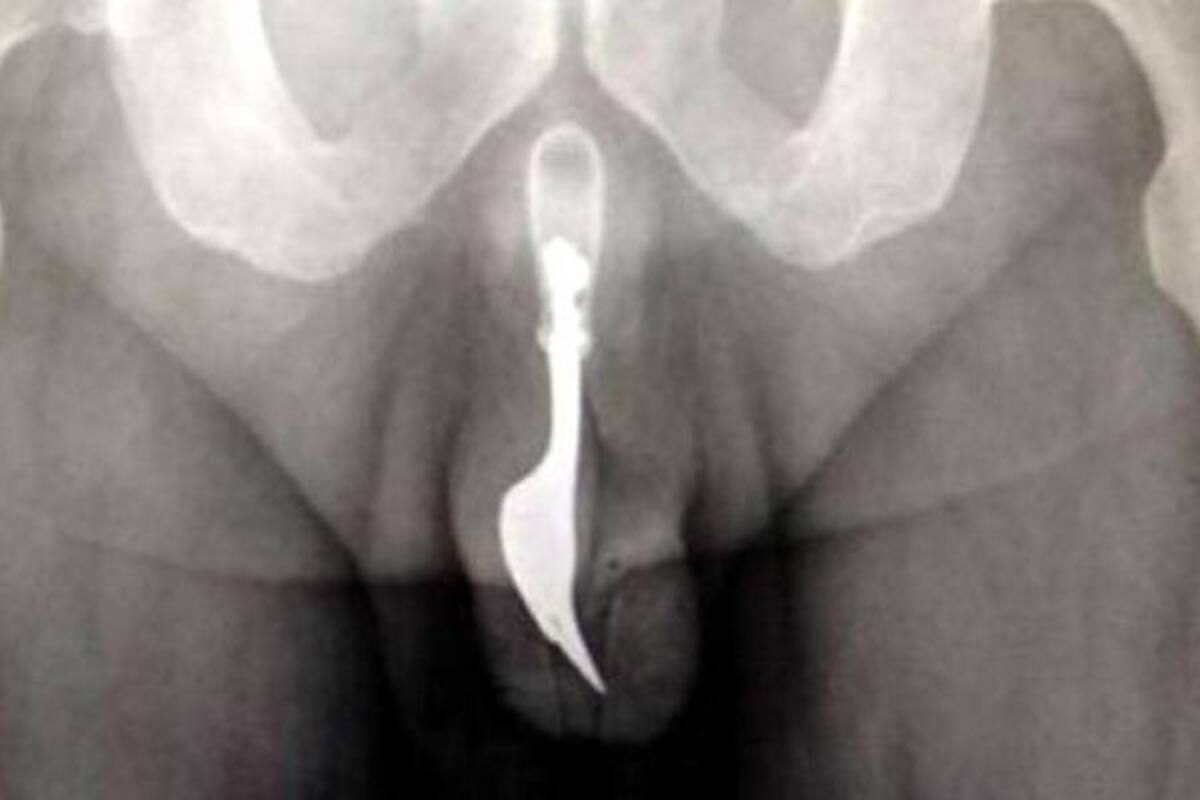

Una increíble visita de urgencia tuvieron que atender médicos del hospital de Canberra (Australia) luego que llegara un hombre de 70 años con un intenso dolor. El sujeto avergonzado y adolorido, según relata 24Horas.cl, fue operado de emergencia para remover un tenedor que había insertado en su pene.

Todo habría sido producto de un juego sexual que terminó con la pieza de 10 centímetros de largo atascada en su apéndice.

El hecho fue publicado en un artículo del International Journal of Surgery Case Reports, donde los profesionales indicaron que el tenedor podía percibirse al tacto y quedó ampliamente revelado por los rayos X.